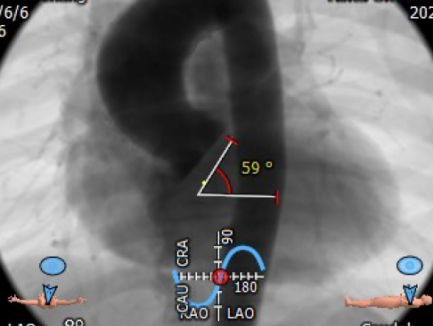

瓣环角度:59°

主动脉根部造影